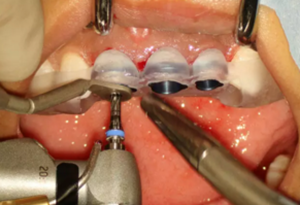

圖8 導(dǎo)板輔助下備洞

(2)即刻種植、即刻臨時修復(fù)。術(shù)中不翻瓣微創(chuàng)拔除牙根,牙槽 窩骨壁完整。在多級導(dǎo)板輔助下完成種植窩洞制備,植入Bego柱形種植 體,型號分別為:上頜右側(cè)中切牙位點(diǎn)4.1mm×15mm、上頜左側(cè)中切牙 位點(diǎn)?3.75mm×15mm、上頜左側(cè)側(cè)切牙位點(diǎn)3.25mm×15mm,扭矩均為 35N·cm。種植體與唇側(cè)骨壁間隙約2mm,植入Bio-Oss®Collagen骨膠 原。戴入橋用鈦臨時基臺,臨時冠就位順利,自凝樹脂口內(nèi)粘接后適當(dāng)修整 外形,充分磨光,調(diào) 至正中 、前伸 和側(cè)方 與對頜牙均無接觸。術(shù)后 根尖片顯示種植體位置、方向良好。